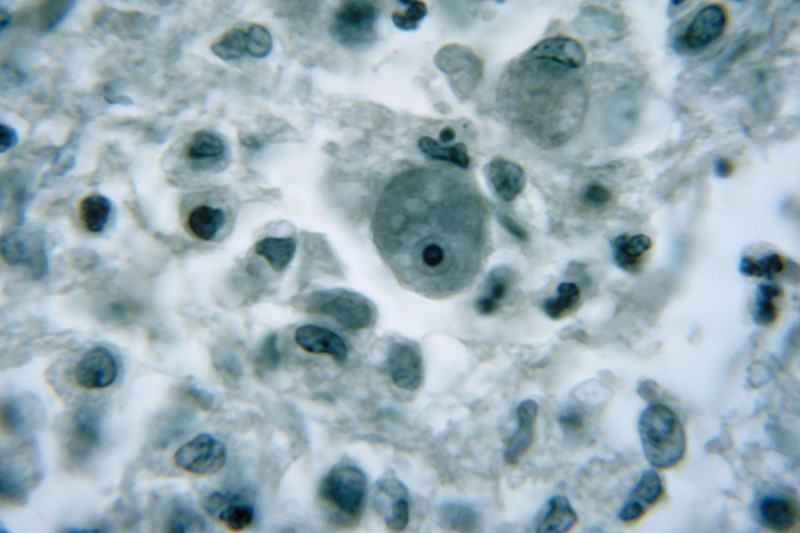

#HazardousMaterials #CrimeInvestigation #Biolab

#PublicHealth #ClimateChange #Amoeba